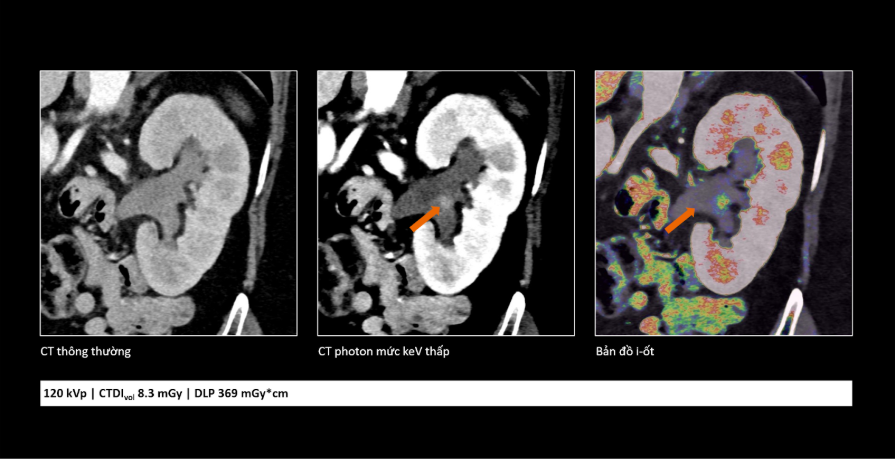

Trong ung thư, việc phát hiện sớm những tổn thương rất nhỏ đóng vai trò quan trọng trong hiệu quả điều trị. Công nghệ cắt lớp vi tính lượng tử cho phép tái tạo hình ảnh với lát cắt rất mỏng (tới 0,2 mm), giúp phát hiện những bất thường mà trước đây có thể bị bỏ sót. Nhờ đó, bác sĩ có thể nhận diện sớm các dấu hiệu bất thường và đánh giá chính xác hơn đặc tính tổn thương, hỗ trợ hiệu quả trong chẩn đoán sớm cũng như theo dõi tái phát.

So sánh cho thấy công nghệ cắt lớp vi tính lượng tử không chỉ giúp hình ảnh rõ hơn mà còn cung cấp thêm thông tin, hỗ trợ bác sĩ đánh giá tổn thương chính xác hơn.